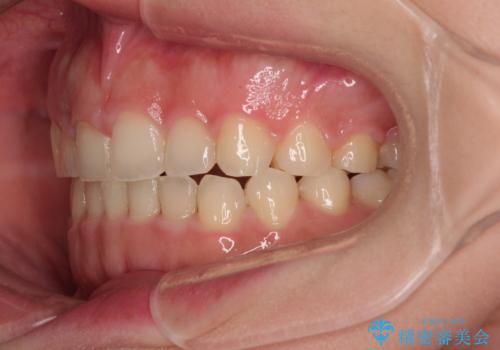

捻れて前に出ている前歯 ワイヤー装置での非抜歯矯正

- 捻れて前に出ている上顎前歯と全体的なデコボコを気にして来院された患者様です。

舌の突出癖がなかなか改善されず、上下前歯が接触するようになるまでに長期間を要しました。